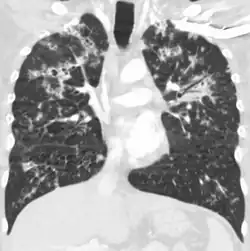

Miliary tuberculosis is a form of tuberculosis that is characterized by a wide dissemination into the human body and by the tiny size of the lesions (1–5 mm). Its name comes from a distinctive pattern seen on a chest radiograph of many tiny spots distributed throughout the lung fields with the appearance similar to millet seeds—thus the term "miliary" tuberculosis. Miliary TB may infect any number of organs, including the lungs, liver, and spleen.[2]

Tuberculosis of the lungs

Testing for miliary tuberculosis is conducted in a similar manner as for other forms of tuberculosis, although a number of tests must be conducted on a patient to confirm diagnosis.[3] Tests include chest x-ray, sputum culture, bronchoscopy, open lung biopsy, head CT/MRI, blood cultures, fundoscopy, and electrocardiography.[9] The tuberculosis (TB) blood test, also called an Interferon Gamma Release Assay or IGRA, is a way to diagnose latent TB. A variety of neurological complications have been noted in miliary tuberculosis patients—tuberculous meningitis and cerebral tuberculomas being the most frequent. However, a majority of patients improve following antituberculous treatment. Rarely lymphangitic spread of lung cancer could mimic miliary pattern of tuberculosis on regular chest X-ray. [14]

A case of miliary tuberculosis in an 82-year-old woman: